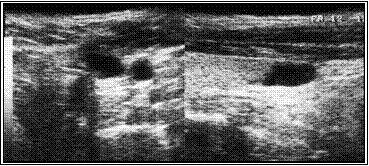

Ниже иллюстрируется клинических случай больной Л, 18 лет. При УЗИ в левой доле обнаружен кистозно-дегенерированный узел 21х9х15 мм. Кистозная дегенерация составила около 75% от объема. При диагностической тонкоигнольной пункционной биопсии дважды получены клетки фолликулярного эпитерия щитовидной железы (кубического и пролиферирующего) и элементы пунктата кистозной полости.

Расчетный объем узла ЩЖ составил 1,4 мл (= 2,1 * 0,9 * 1,5 * 0,52).

Под контролем УЗИ больной произведена пункция узла, аспирировано около 0,5 кистозного содержимого, после чего в полость образований введено 1.0 мл этилового спирта, что составило около 2/3 от расчетного объема узла.

На приведенных ниже эхограммах демонтрируется динамика регрессии в течение года.

А. Эхограмма до склеротерапии

Б. Эхограмма через три месяца после склеротерапии